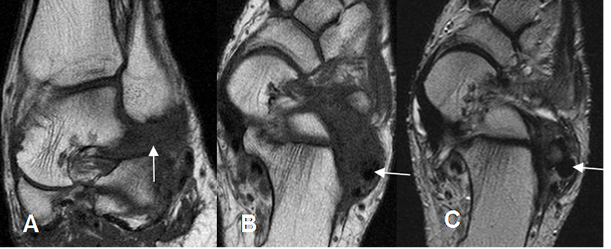

Fig 108. Sindrome del seno del tarso.

A: RM coronal en T1. Imagen hipointensa localizada en el seno del tarso, que reemplaza la grasa.

B: RM axial en T1 y C: RM axial en T2. Tejido inflamatorio en el seno del tarso, hipointenso en ambas secuencias por fibrosis crónica, que rodea los tendones peroneos (Flechas).